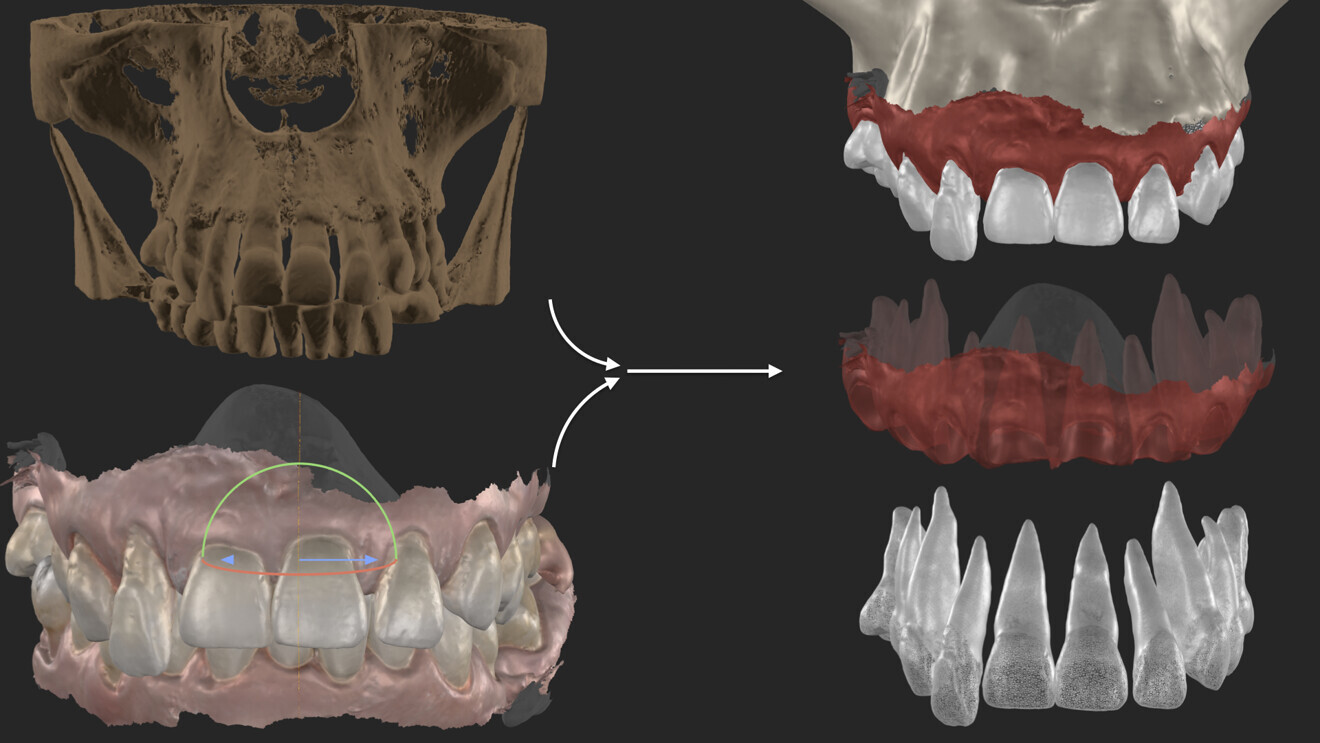

Fig. 6: Combination of the CBCT and the intra-oral scans for segmentation.

For effective 3D planning, having a combined extraction model is essential. This provides the dental technician with clear reference points for creating custom support that follows the emergence profile of each individual tooth (Figs. 6 & 7).

In this specific case, we strategically positioned the design palatally and more coronally. This compensated for the existing occlusal disharmonies while also shaping the soft tissue for prosthetically guided healing of the extraction sites. By integrating these adjustments, we could harmonise the patient’s bite and smile, achieving both function and aesthetics (Figs. 8–10).